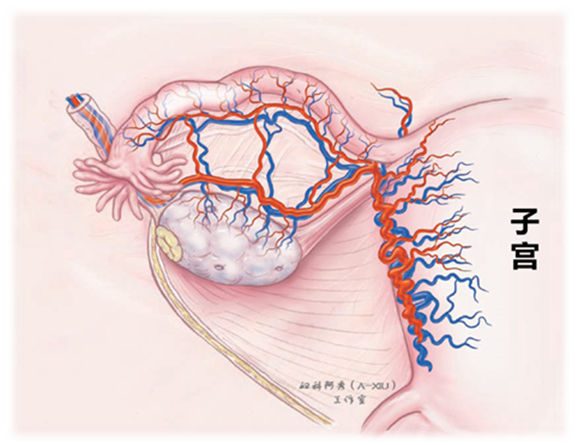

附件的处理分为输卵管切除和附件切除,要点在于手术时要熟悉所有的血管分布,这样才能做到术野干净,“刀不血刃”,否则可能“血肉模糊”。

2.1 如图所示,我们可以看到输卵管系膜的血管位置,切除输卵管时,注意紧贴输卵管切除,这样可以避开血管网,超声刀切开基本不出血。推荐使用超声刀切开以后,双极电凝系膜残端,避免延迟出血。(图5)